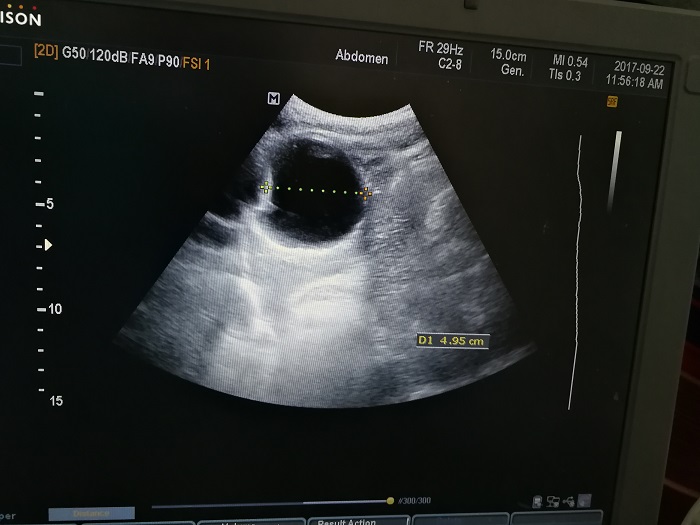

扎西(化名),男,15歲,包蟲病篩查陽性,牧區孩子,家里有牦牛20頭、羊200只,狗1條,牛羊自家屠宰,飲用河水。

●革吉縣初級中學篩查點 · B超現場圖片

除了包蟲病篩查外,連續三天的學校體檢我醫療隊發現腎積水、腎囊腫、腎結石的學生患者較多,我們將體檢到的相關臟器疾病同時間反饋給了班主任,讓他們密切觀察病情,及時通知家長。劉冬梅醫生建議,學校要組織學生多飲水,同時多加觀察本地水質情況。

本次篩查,革吉縣初級中學共篩查學生498例,陽性3例,疑似2例。